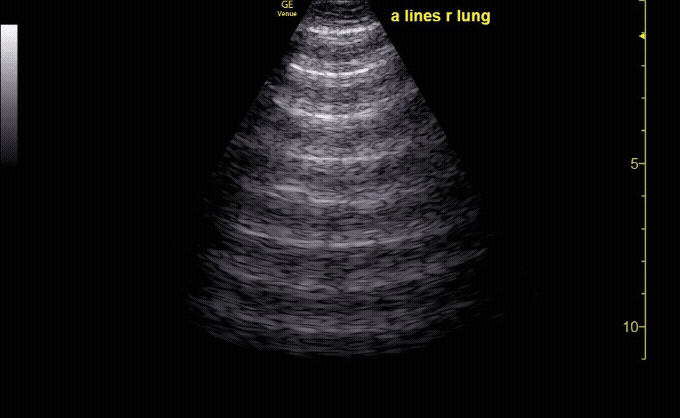

Reverberation Artifact: appears as multiple, equally spaced echoes caused by sound bouncing back and forth between two strong reflectors, such as the pleura (seen here) or a needle.

c/o John Elue, MD